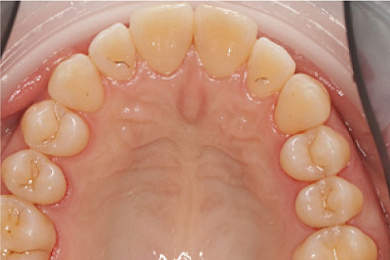

- Затем проводится удаление мягкого налёта аэрозольным методом: зубы обрабатываются составом: вода с мельчайшими абразивными частицами бережно очищает поверхность зубов от налёта. Благодаря этой процедуре зубы становятся светлее сразу на 1-2 тона.

Результат лечения